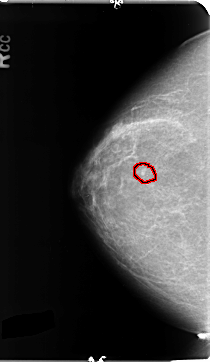

B_3124_1.RIGHT_CC

RIGHT_CC LINES 4704 PIXELS_PER_LINE 2720 BITS_PER_PIXEL 12 RESOLUTION 50 OVERLAY

FILE: B_3124_1.RIGHT_CC.OVERLAY

TOTAL_ABNORMALITIES 1

ABNORMALITY 1

LESION_TYPE CALCIFICATION TYPE PLEOMORPHIC DISTRIBUTION CLUSTERED

ASSESSMENT 4

SUBTLETY 2

PATHOLOGY BENIGN

TOTAL_OUTLINES 1

BOUNDARY